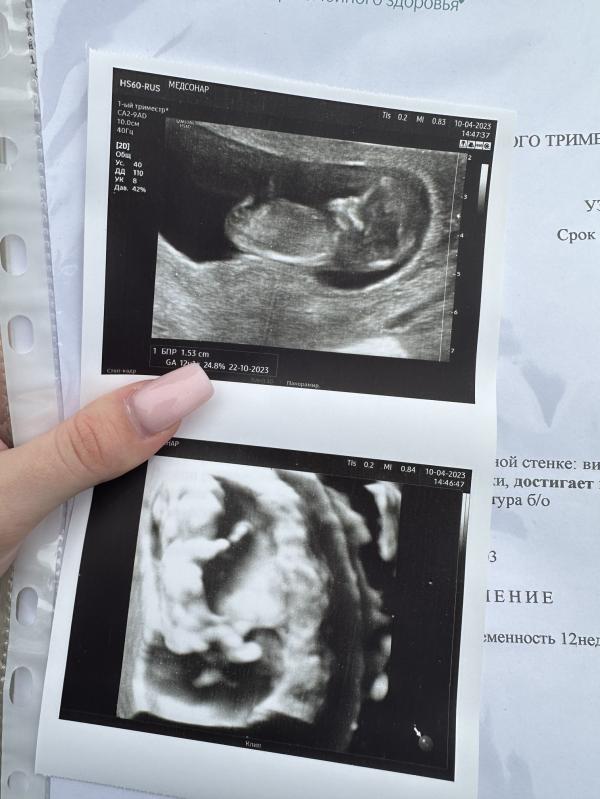

Наш маленький круассанчик развивается хорошо, все в срок! Врач сказал, что может предположить пол, но я отказалась, буду сдавать кровь и впереди нас ждёт гендер пати, к которому уже давно готовимся 🥰 Малыш очень активный, миллион поз в секунду, лежит как папа, закинув одну ручку за голову (на втором фото видно) 😂 Если Вы тут видите пол, то не пишите пожалуйста, хотим сюрприз, но внутри у меня уже есть чувство по поводу пола малышика 🥹